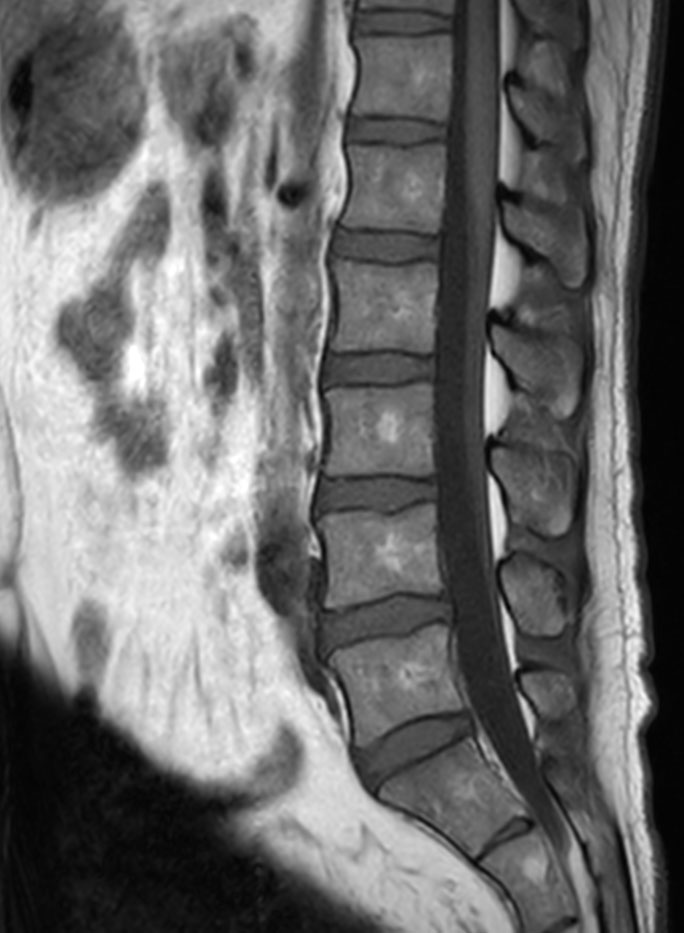

Patient with a lumbar neurography schwannoma.